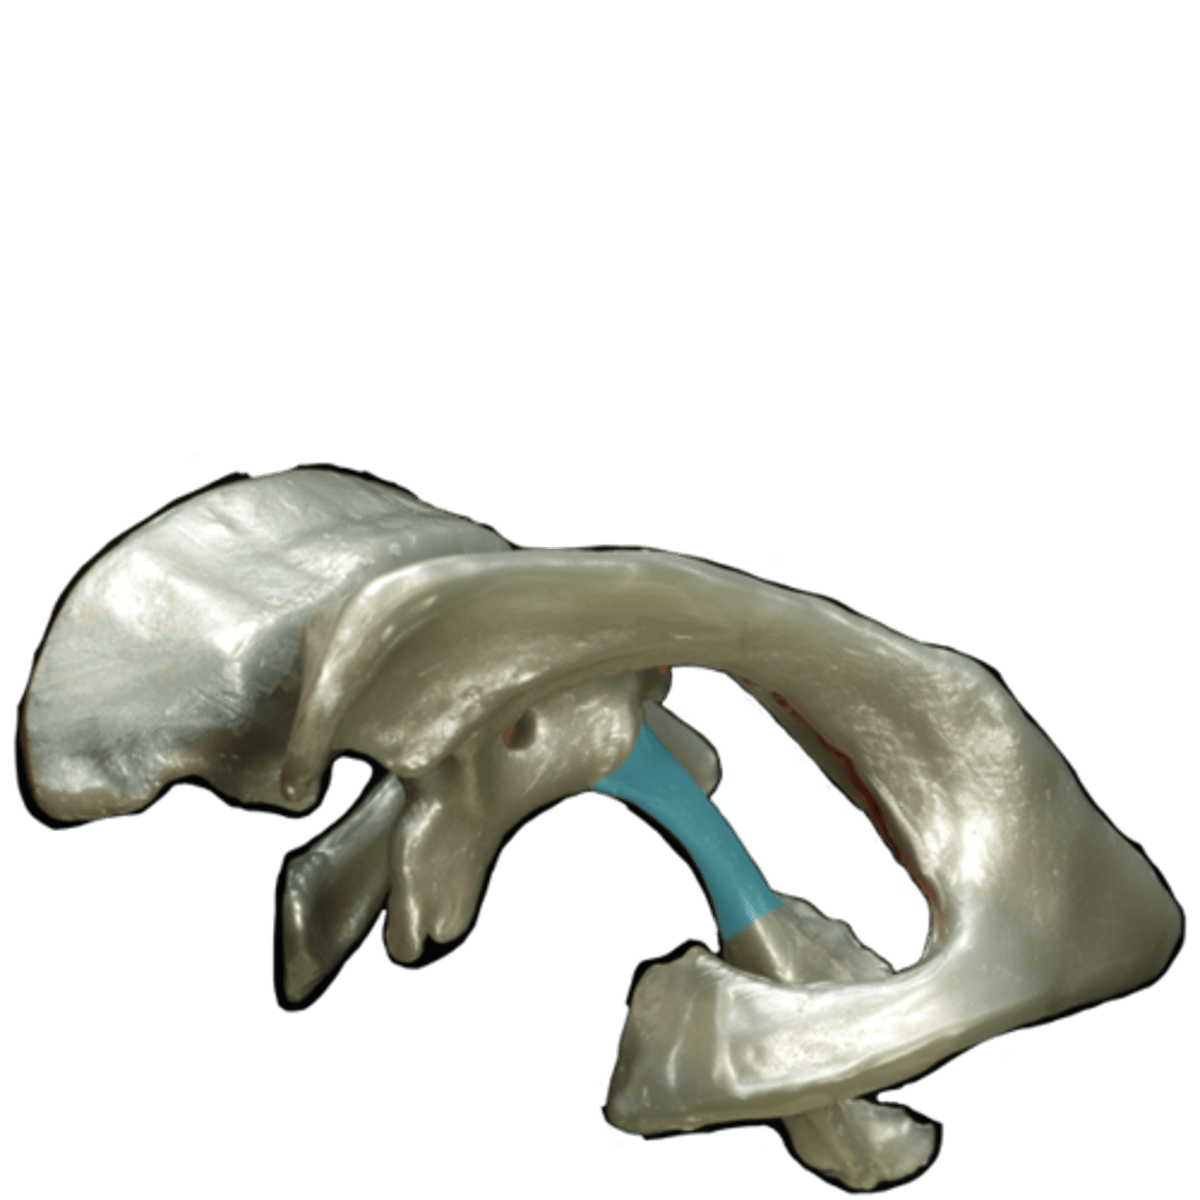

Basal Ganglia

structures in the forebrain that help to control movement. Composed of three main parts: the caudate nucleus, the putamen, and the globus pallidus

Caudate nucleus

One of the major nuclei that make up the basal ganglia. Head: Anterior to the thalamus, forming the lateral wall of the lateral ventricle.

Body: Extends posteriorly and laterally from the head, parallel to the thalamus.

Tail: Curves inferiorly and medially, lying above the temporal horn of the lateral ventricle.

Putamen

involved in motor control and learning

Globus Pallidus

more medial than putamen, appears with the third ventricle.

internal capsule

White matter pathway is lateral to the caudate nucleus, between the caudate and the putamen (and globus pallidus). It carries primarily motor fibers, including corticospinal tract fibers.